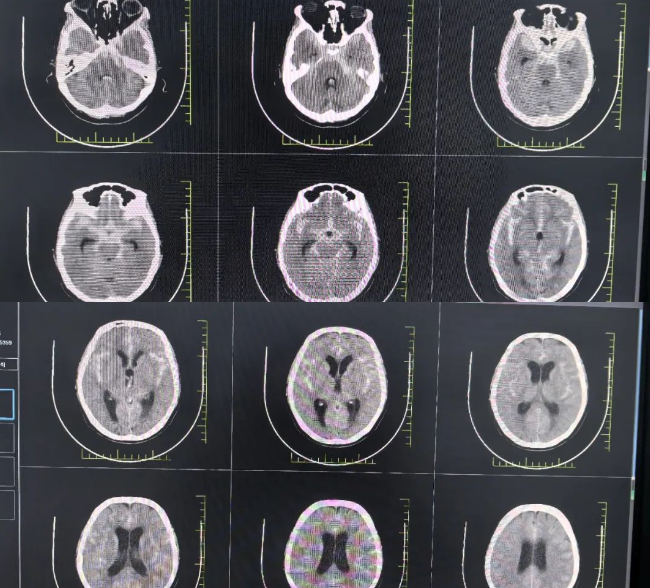

*影像檢查蛛網(wǎng)膜下腔出血

長春國文醫(yī)院神經(jīng)介入團隊接到通知后,即刻啟動 “腦卒中綠色通道”。通過頭部 CTA 檢查,精準鎖定了前交通位置一枚 8mm 的動脈瘤,且伴有兩個子囊。在麻醉科、導管室、影像科等多學科的緊密協(xié)作下,主刀醫(yī)生僅用 43 分鐘便完成了微創(chuàng)栓塞手術(shù),成功拆除了這顆破裂的 “顱內(nèi)炸彈”。

顱內(nèi)動脈瘤破裂出血,素有 “腦內(nèi)不定時炸彈” 之稱。首次破裂死亡率高達 35%,二次破裂死亡率更是飆升至 70%。在此次救治中,國文醫(yī)院建立的 “急救閉環(huán)” 發(fā)揮了關(guān)鍵作用。從快速完成 CTA 確診,到將確診至股動脈穿刺的時間縮短至 52 分鐘,遠遠快于國際指南要求的 90 分鐘標準。團隊運用三維旋轉(zhuǎn)造影技術(shù),以 0.17mm 的分辨率清晰呈現(xiàn)瘤體形態(tài),并結(jié)合智能血流動力學分析系統(tǒng),為制定精準的栓塞方案提供了雙重保障。